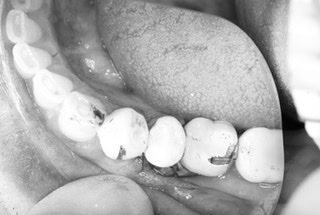

患者さんは他院でのインプラントオペの経験がある方ですが、『ビックリするぐらいスムーズに終わった』と喜んでおられました。

その後は密着具合を示す値も良く、即日に仮歯まで装着してお帰り頂きました。